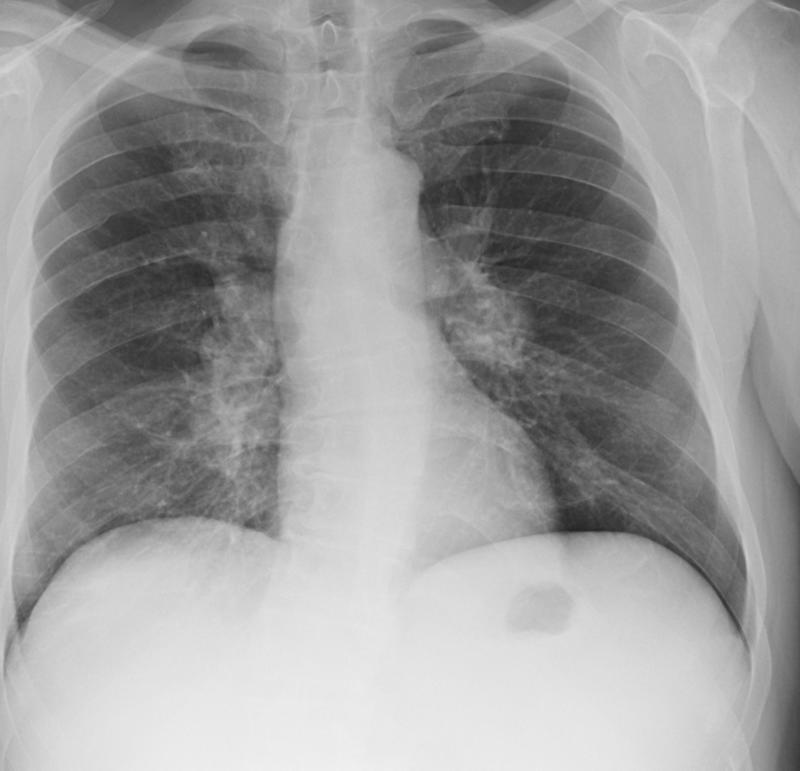

Lymphoma   Nodes and splenomegaly